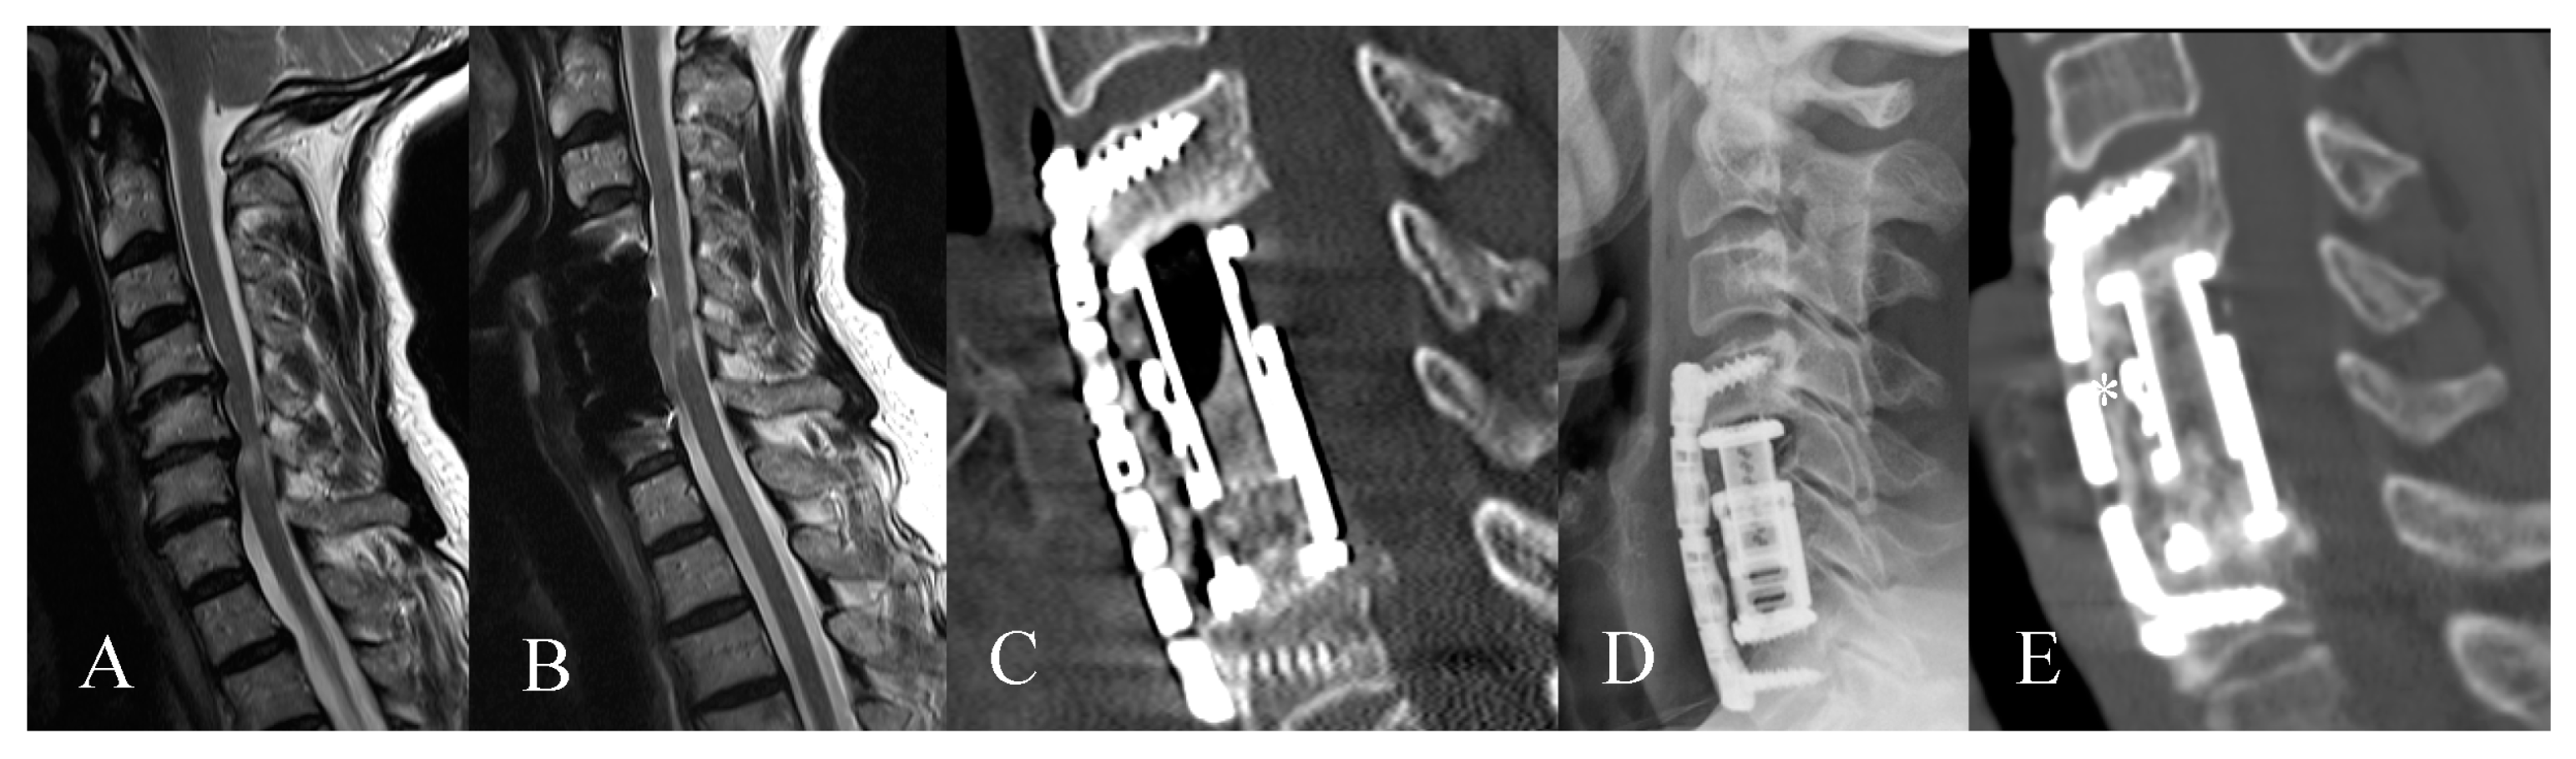

3.2. Radiological Outcome

3.3. Complications